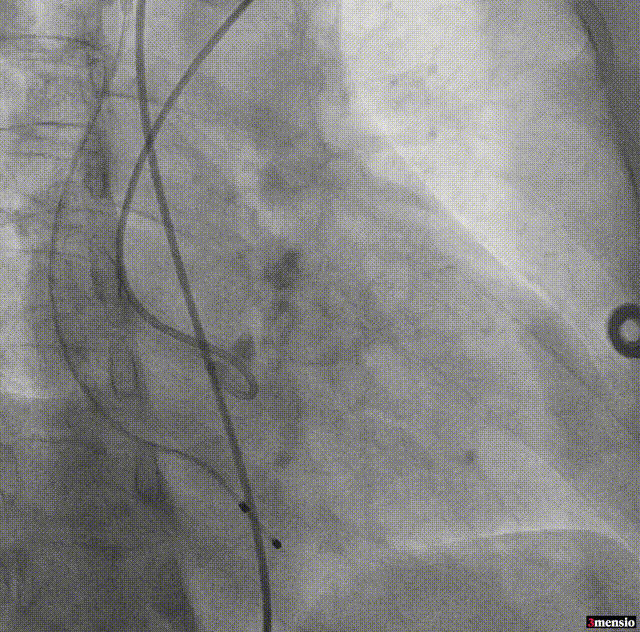

SENTINEL抗栓塞脑保护装置

良好的调弯性能,轻轻拉动圈套器即可轻松过弓

横位心68°升主扩张且右无局部粘连,圈套器辅助跨瓣